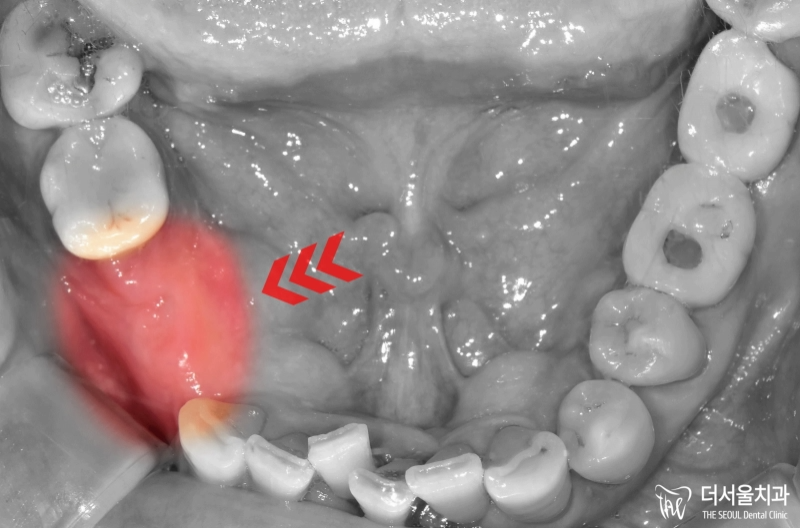

안녕하십니까, 더서울 문정동치과 쌍둥이 박현성 원장입니다. 사랑니라는 치아가 생겼을때, 의료진들은 되도록 빠른 시일 내에 빼는 것이 좋다 그렇게 알려드리고

우리가 흔히 말하는 사랑니 는 맨 뒤에 있는 큰 어금니로 전문용어로 ‘제3대구치’라고 부르고 있습니다. 사실 관리만 잘하면 치아를 뽑지